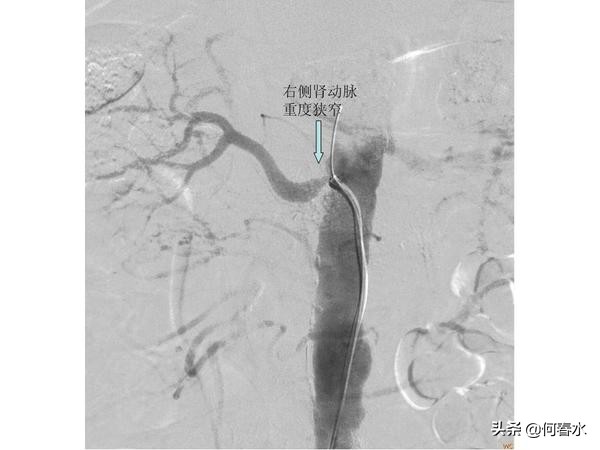

患者至今随访5年,支架通畅,头晕等脑缺血症状完全消失。但是春节后再次出现头晕不适,在职工医院检查发现右侧颈动脉重度狭窄,右侧颅内梗塞病灶,左侧颅内未有梗塞病灶。入住我科后,造影检查发现:右侧颈动脉重度狭窄伴有溃疡形成,左侧颈动脉支架通畅,右侧肾动脉重度狭窄。

(3)血管健康管理的重要性:患者有糖尿病、高血压、吸烟,5年来血管病变不断发展,直至累及右侧颈动脉和右侧肾动脉,面临再次脑中风及右肾功能丢失的风险,右侧颈动脉支架及右侧肾动脉支架避免了风险的发生,但是患者必须戒烟及严格控制血压,血糖,以防血管病变累及更多的血管;